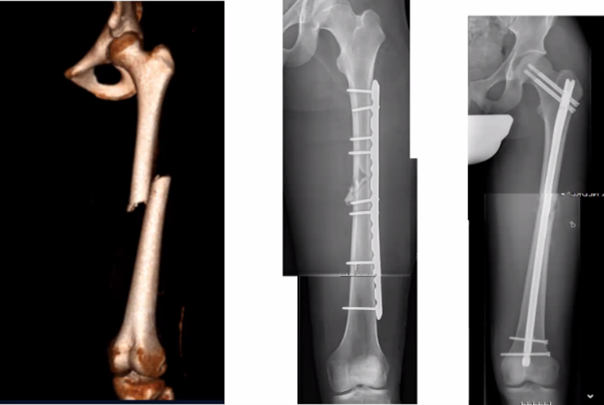

Olika metoder vid denna femurfraktur

Vad ser du, vad ska vi i regel välja?

A

• Lång platta för direkt läkning (kompressions-osteosyntes)

• Märgspik – indirekt läkning

o Väldigt bra. Tillåter belastning direkt (bra)

o Om märghålan är för smal så kör vi platta (annars alltid spik!)